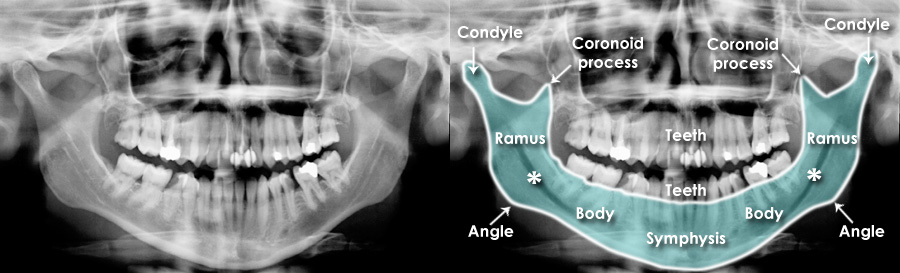

Dislocated Jaw X Ray Collection 2022 Dislocated Jaw X Ray Collection 2022

Dislocated Jaw X Ray

Learning Radiology - Dislocated, Mandible, Mandibular, Dislocation Dislocated Jaw: Symptoms and Treatment Bilateral temporomandibular joint dislocation | Radiology Case ... Pretreatment X-ray showing the anterior dislocation. | Download ... Learning Radiology - Dislocated, Mandible, Mandibular, Dislocation Dislocated Jaw X Ray